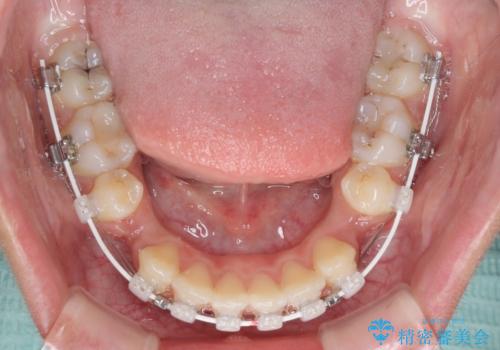

- 上下の出っ歯を気にして来院された患者様です。

口元を積極的に引っ込めるために、上下左右の第一小臼歯を4本抜歯することとしました。

前歯部の突出と開咬は、舌突出癖によるものでしたので、舌のトレーニングをしっかりと行っていただき、1年半程度と短期間で治療を終えることができました。